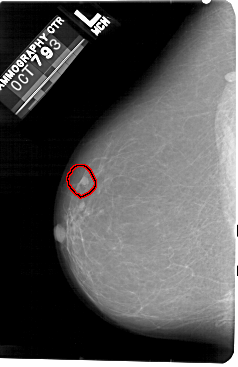

A_1476_1.LEFT_CC

LEFT_CC LINES 5491 PIXELS_PER_LINE 3556 BITS_PER_PIXEL 12 RESOLUTION 43.5 OVERLAY

FILE: A_1476_1.LEFT_CC.OVERLAY

TOTAL_ABNORMALITIES 1

ABNORMALITY 1

LESION_TYPE MASS SHAPE ROUND MARGINS CIRCUMSCRIBED

ASSESSMENT 4

SUBTLETY 4

PATHOLOGY BENIGN

TOTAL_OUTLINES 1

BOUNDARY